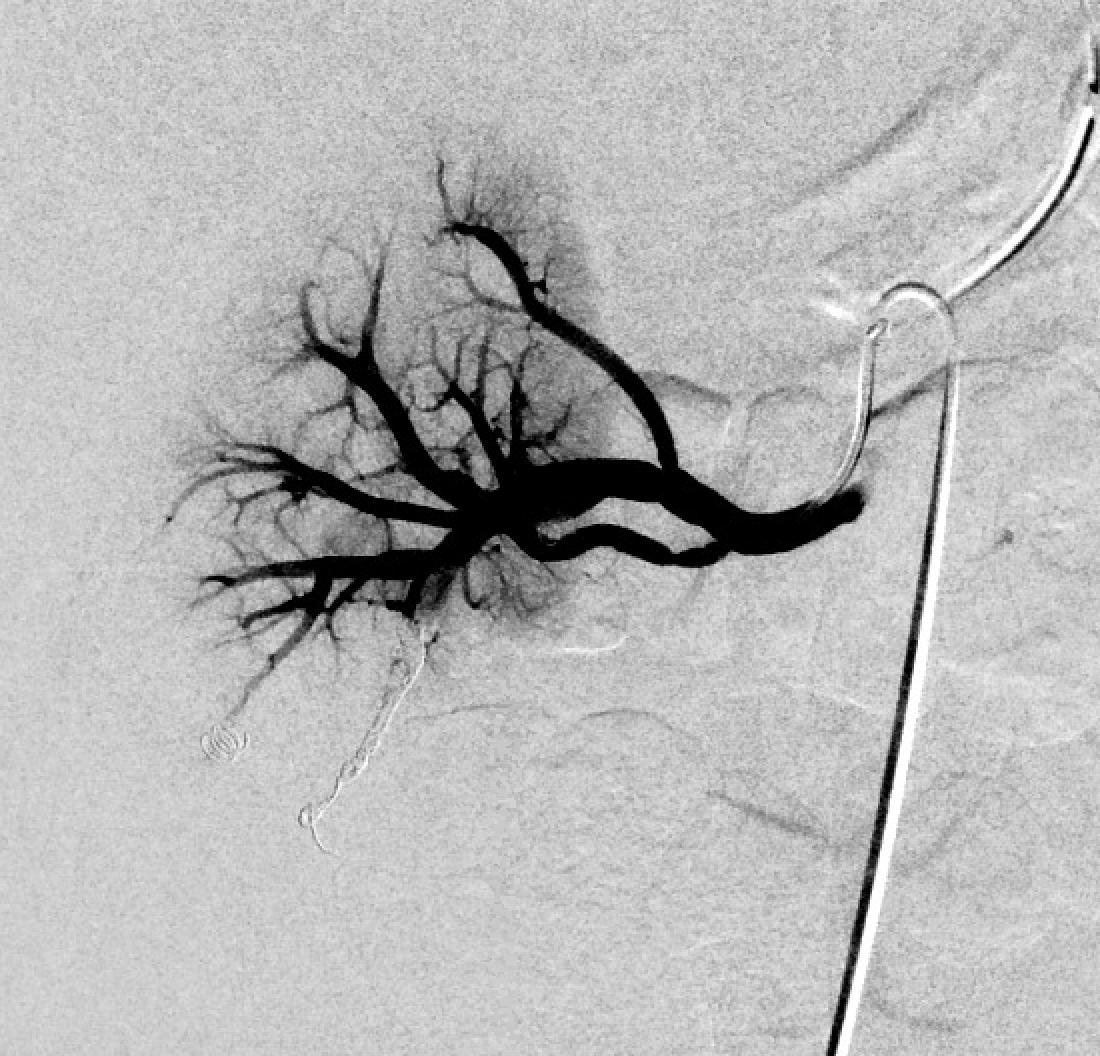

Huge renal PSA 9 days post pNX w/ persistent hematuria. Coiling starts in the outflow! Back door --> Front door or risk continued bleeding! Double team w/ Christopher Kim #ImpeccableCoilTechnique #SoMuchKidneyLeft! #iRad Vascular Institute of Atlantic Medical Imaging @AMIRadiology @MdPetruzzi Alexandria CVIR @ABrandisVIR

Huge renal PSA 9 days post pNX w/ persistent hematuria.  Coiling starts in the outflow!  Back door --&gt; Front door or risk continued bleeding! Double team w/ <a href="/cek_VIR/">Christopher Kim</a> #ImpeccableCoilTechnique #SoMuchKidneyLeft! #iRad <a href="/AMI_Vascular/">Vascular Institute of Atlantic Medical Imaging</a> @AMIRadiology @MdPetruzzi <a href="/AlexCVIR/">Alexandria CVIR</a> @ABrandisVIR